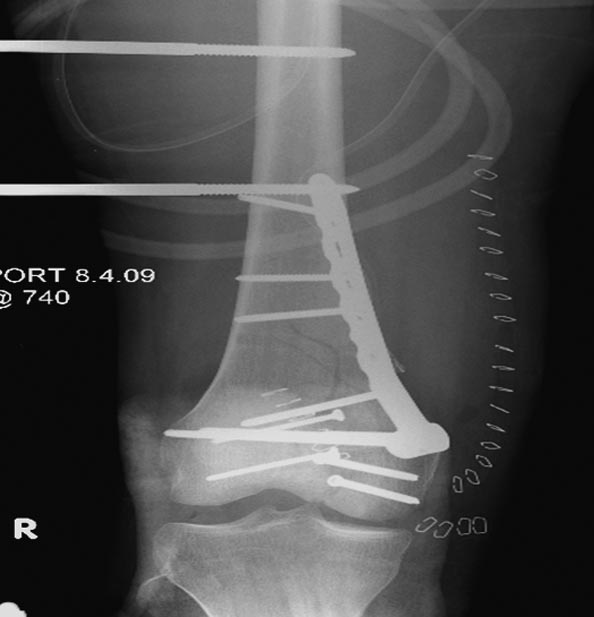

Раны в области коленного сустава и на плече до сих пор чистые, остаются

открытыми. Отсутствует признаки инфекции, решили превратить недостаток в

преимущество, т.е. фиксировать через открытые раны пластинами.

На 9й день фиксация дистального бедра, где фрагмент Hoffa и вертикальный

перелом надколенника, зафиксированы винтами.